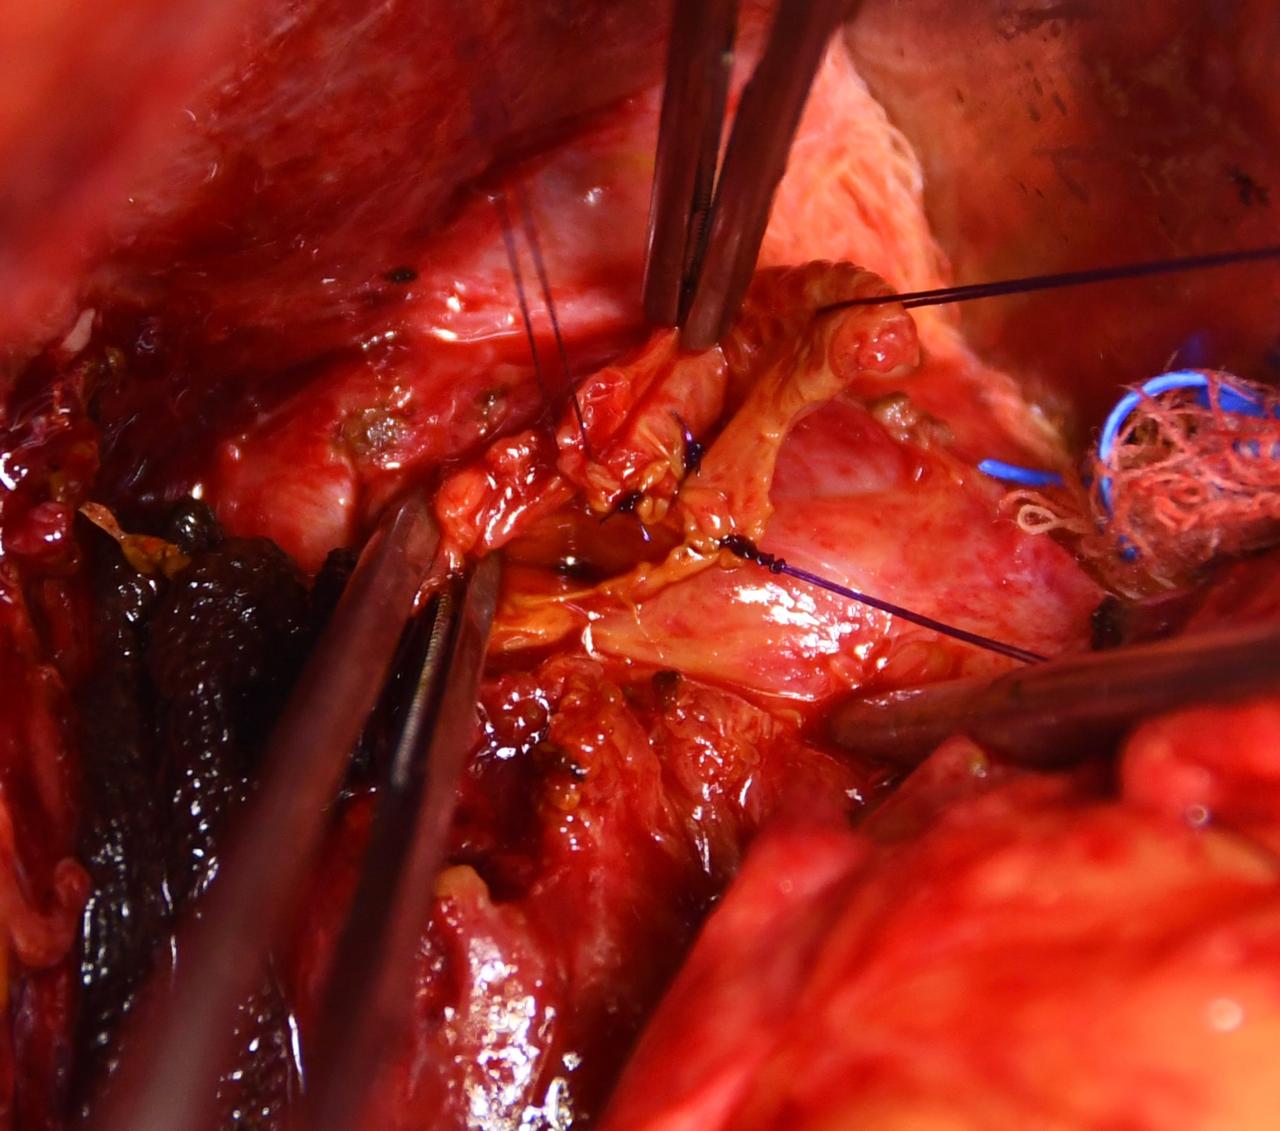

Galería

Cirugías realizadas con éxito